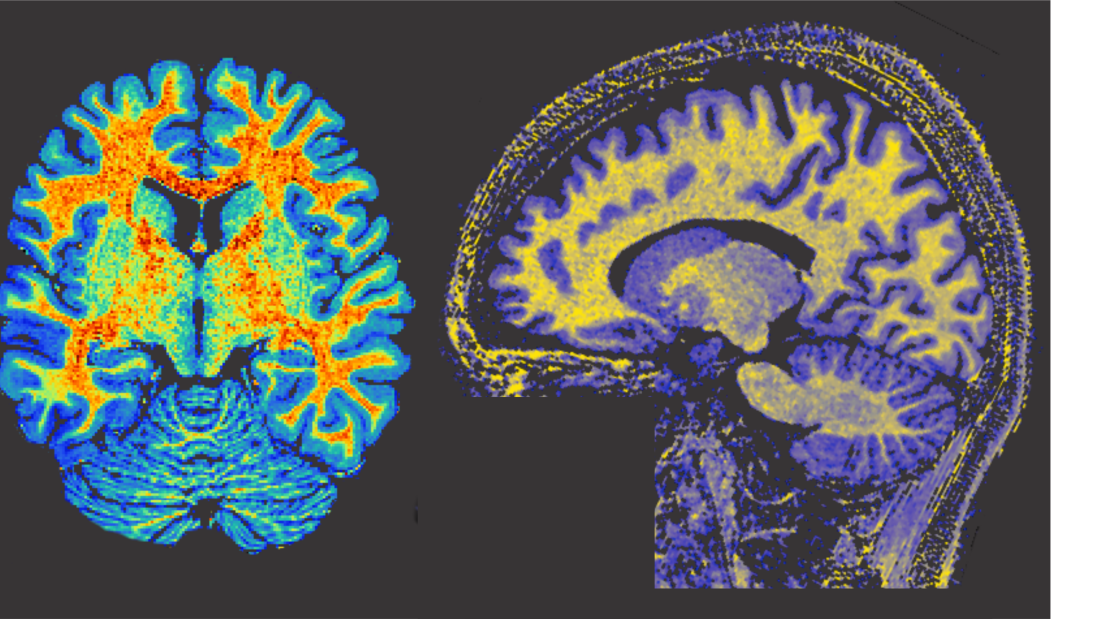

Mae’r gwaith ymchwil arloesol i niwrowyddoniaeth, sy'n cyfuno delweddu ymennydd uwch â dadansoddiad ymddygiad manwl, er mwyn deall yn well achosion atal dweud a gwella opsiynau triniaeth yn y dyfodol.

Dywedodd Dr Charlie Wiltshire, sy’n Ddarlithydd mewn Seicoleg yn Adran Seicoleg Prifysgol Bangor, "Bydd gan tua 8% o bobl atal dweud ar ryw adeg yn eu bywydau, ac i lawer, mae deall ei achosion a dod o hyd i driniaethau effeithiol yn parhau i fod yn brif flaenoriaeth." Bydd y grant hwn yn cefnogi ein hymchwil drwy ddefnyddio delweddu cyseiniant magnetig uwch a thrwy fesur cemeg yr ymennydd i ddeall sut mae cynhyrchu lleferydd yn cael ei reoli a sut mae'r prosesau hyn yn wahanol mewn pobl sydd ag atal dweud. Rwy'n hynod o ddiolchgar i’r Academi Gwyddorau Meddygol am eu cefnogaeth, sy'n fy helpu i ddatblygu fy labordy a gweithio mewn partneriaeth â phobl sydd ag atal dweud i wella ein dealltwriaeth o niwrowyddoniaeth atal dweud.”